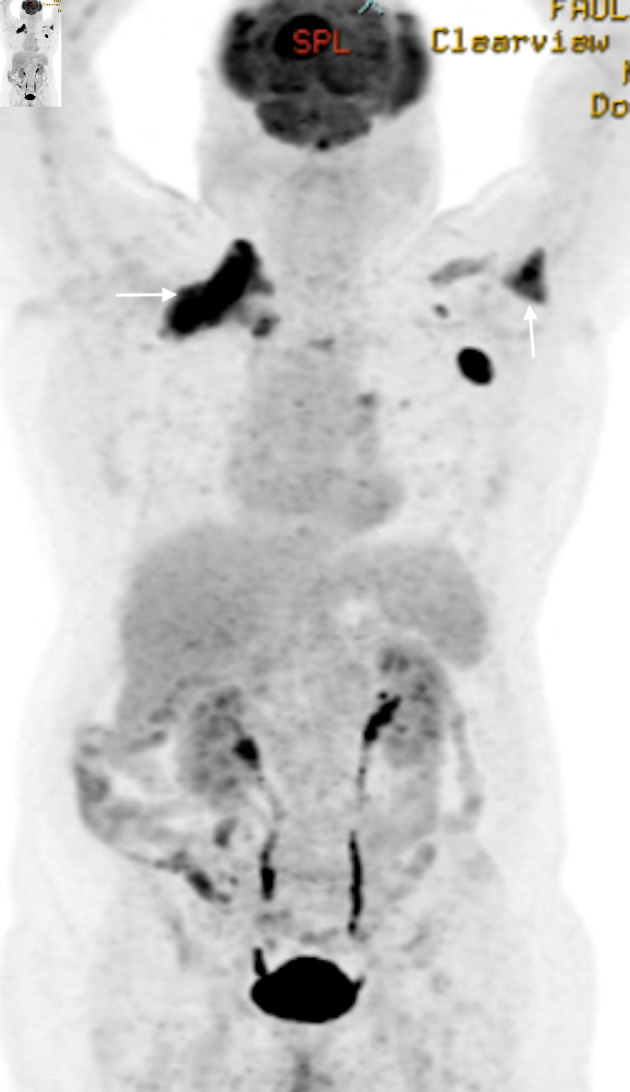

外周T细胞淋巴瘤(PTCL-NOS)是一种罕见的侵袭性非霍奇金淋巴瘤(NHL)亚型,起源于成熟的T细胞或自然杀伤细胞(NK),约占所有NHL病例的5%。虽然PTCL-NOS通常累及淋巴结,但结外部位如皮肤、胃肠道、肝脏和肺部也可能受到影响。中枢神经系统(CNS)受累是极其罕见的,特别是在最初的表现。当它确实发生时,最常受影响的是大脑,其次是脊髓和脑膜。我们报告一例罕见的PTCL-NOS合并继发性中枢神经系统淋巴瘤累及脑膜的病例。我们的病人是一名75岁的男性,患有多种合并症,表现为几周的间歇性头痛。影像学显示多发性轴外脑病变,浸润到颅外软组织、硬膜外间隙、脑膜和脑实质。随后的淋巴结活检证实PTCL-NOS。他开始使用利妥昔单抗、环磷酰胺、阿霉素、长春新碱和强的松(R-CHOP),并计划使用大剂量甲氨蝶呤。此后,患者因各种并发症多次再次入院,并在诊断后约2.5个月死亡。我们得出结论,PTCL-NOS继发性中枢神经系统受累非常罕见,预后较差,中枢神经系统诊断后的中位生存期约为1.1个月。早期诊断和量身定制的治疗策略,包括中枢神经系统穿透剂,是必不可少的。需要继续研究以更好地了解和改善这种侵袭性疾病的结果。

Peripheral T-cell lymphoma, not otherwise specified (PTCL-NOS), is a rare and aggressive subtype of non-Hodgkin lymphoma (NHL) that arises from mature T or natural killer (NK) cells, accounting for about 5% of all NHL cases. While PTCL-NOS typically involves lymph nodes, extranodal sites such as the skin, gastrointestinal tract, liver, and lungs can also be affected. Central nervous system (CNS) involvement is extremely rare, especially at the time of initial presentation. When it does occur, the brain is most commonly affected, followed by the spinal cord and meninges. We present a rare case of PTCL-NOS with secondary CNS lymphoma involving the meninges at initial diagnosis. Our patient is a 75-year-old male with multiple comorbidities who presented with several weeks of intermittent headaches. Imaging showed multiple extra-axial brain lesions with infiltration into extracranial soft tissues, epidural space, meninges, and brain parenchyma. A subsequent lymph node biopsy confirmed PTCL-NOS. He was started on rituximab, cyclophosphamide, doxorubicin, vincristine, and prednisone (R-CHOP), with plans for high-dose methotrexate. Thereafter, the patient was readmitted several times due to various complications and expired approximately 2.5 months after diagnosis. We conclude that secondary CNS involvement in PTCL-NOS is very rare and has a poor prognosis, with a median survival after CNS diagnosis of about 1.1 months. Early diagnosis and tailored treatment strategies, including CNS-penetrating agents, are essential. Continued research is needed to better understand and improve outcomes for this aggressive disease.